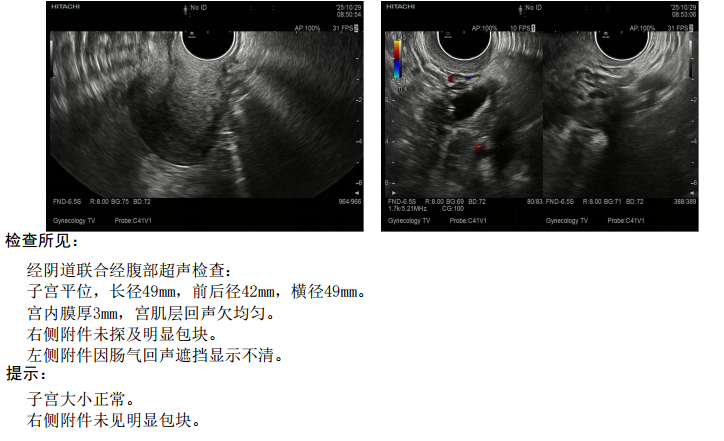

术后予戈舍瑞林6针治疗,第三针起添加坤泰胶囊。2025年10月29日复查妇科超声未见明显复发。

妇科超声